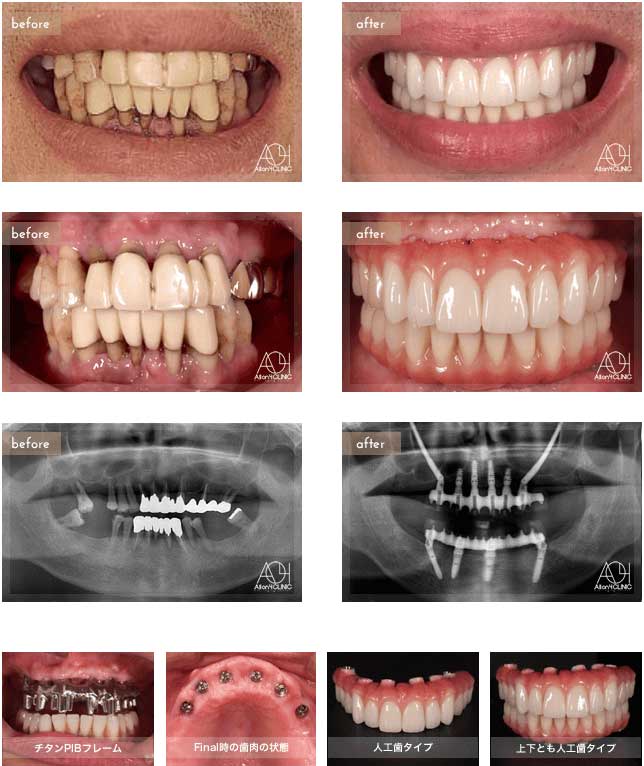

Treatment : All-on-4 zygoma

- Upper All-on-4

- Lower All-on-4

Age : 56 Sex : 男 S.T

| 主訴 | 仕事が忙しく歯には全く関心が無く、とうとう食事が困難になり治療を受ける事を決意。 |

| 治療内容 | ガイデッドサージェリーにてインプラント埋入。極めて骨量が少ないためザイゴマインプラントにて治療 |

| 治療費(総額) | ¥7,200,000(税抜)『モニター割引適用』 |

| リスク | 治療後の口腔管理が不適切な場合、埋入したインプラント周囲に感染・炎症を起こし、脱落する可能性がございます。 |